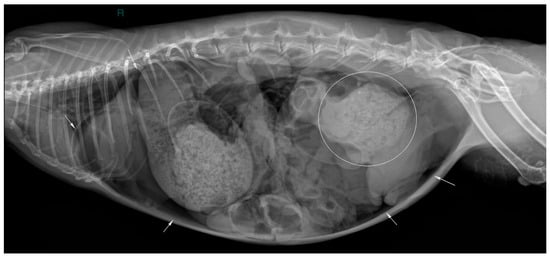

2. Case Description